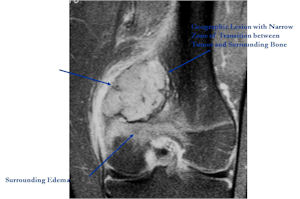

MRI:

- Also useful in determining extent

- There is often extensive edema around the tumor in the surrounding bone and soft tissues that can lead to a misdiagnosis of a malignant tumor.

- Most have a similar radiographic appearance as a conventional osteoblastoma and have well defined margins, variable amounts of mineralization and peritumoral sclerosis. They occasionally have radiographic characteristics consistent with malignancy.